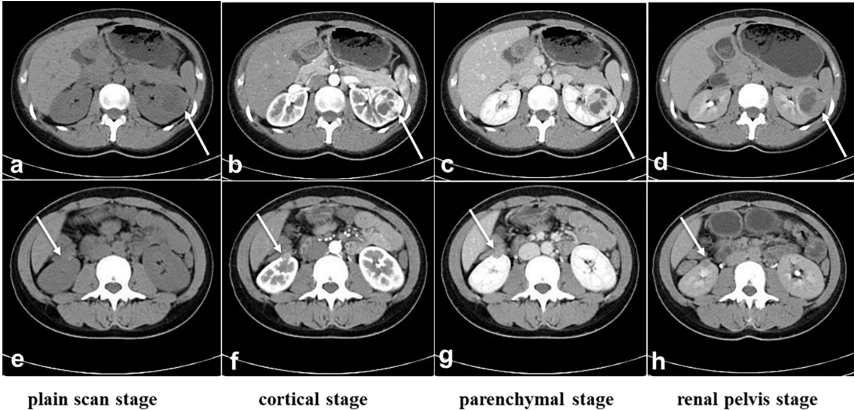

一名25岁女性,在常规检查时,通过超声波检测出双侧肾肿瘤。患者没有腰痛、血尿、发烧和其他症状,体重也没有明显变化。体格检查(PE)显示无阳性体征,皮肤粘膜正常,无结节。彩超结果显示,考虑到子宫肌瘤的可能性,子宫实质有一个异常回声区(7mm×6mm),边界清晰,形状规则,以低回声为主,无血流信号。计算机断层扫描(CT)结果显示一个软组织肿块(36 mm×37 mm×37mm)伴钙化,左肾实质内发现不均匀强化,突入肾包膜,靠近脾脏和胰腺。右肾下极还发现一个结节状软组织(12 mm×12 mm×13 mm),该软组织向外延伸至肾包膜,并靠近肠道;TNM阶段为T3aN0M0(图1)。

图1. 术前CT检查。(A-D):左肾肿瘤的位置和大小。(E,F):右肾肿瘤的位置和大小。